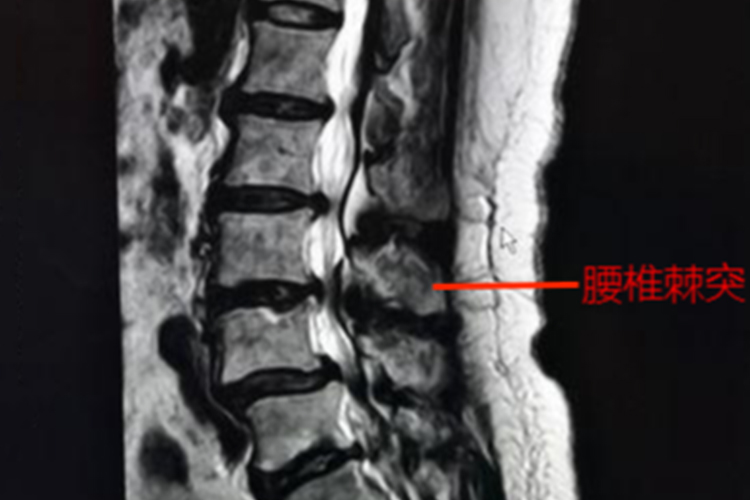

腰椎棘突是腰椎的一部分,是骨头后方的一个凸起,呈方形扁平状,能帮助增加椎体稳定性,也常选做手术穿刺部位。

腰椎位于腰的后部正中,棘突是腰椎的一部分,呈长方形扁板状,水平位伸向后,末端增厚易于触及,棘突的下方如梨状,为多裂肌肌腱附着处,末端膨大,为棘上韧带附着处。各腰椎棘突间稍显凹陷,肌肉越发达者则凹陷越明显。

腰椎棘突是骨骼的正常结构,其具有杠杆作用,众多肌肉、韧带附着其上,更增加了脊柱的稳定性。相邻棘突间空隙较大,在临床也易选做手术的穿刺部位。